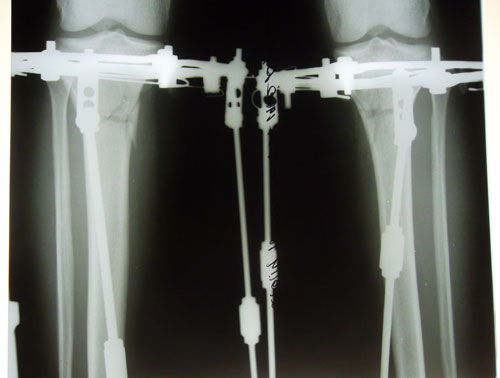

Рентген в 2 месяца.

Сращение отличное, снимать можно в первых числах апреля, но Н.Н. будет отсутствовать с 1 - 14 апреля. По этому, рекомендую приехать на снятие аппаратов 15 апреля (так будет лучше).

Дата операции 08.01.2014г.

Дата снятия аппаратов 15.04.2014г.

Срок лечения 98 дней.